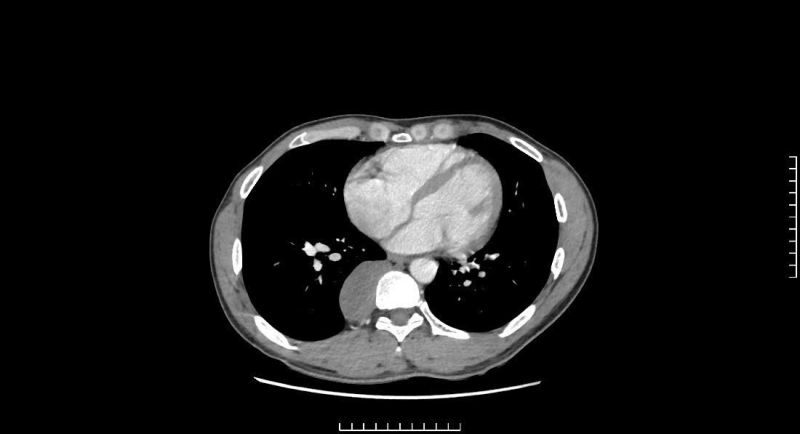

Patienten opererades för en bakre mediastinumtumör på Bai Chay-sjukhuset och återhämtade sig väl.

Med hjälp av modern endoskopisk kirurgisk utrustning närmade sig kirurgen tumören som mätte cirka 5x10 cm, med en fast densitet som sträckte sig från ryggraden D7-D11. Efter 3 timmar var operationen säker och framgångsrik, den bakre mediastinumtumören avlägsnades helt, lungorna expanderade väl, inga luftläckor och ingen lymfvätska utsöndrades. Efter 5 dagars operation återhämtade sig patientens hälsa väl.